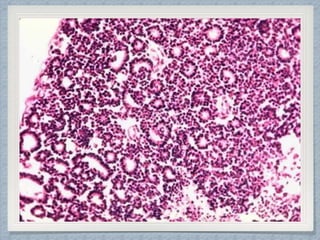

Cytology Findings

Gross Findings

Ewing’s Sarcoma